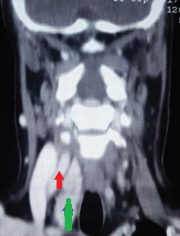

Neck SPECT/CT. Green arrow — Ectopic (within the sheath) parathyroid adenoma. Red arrow — Right common carotid artery (Courtesy Dr. V. Penopoulos)